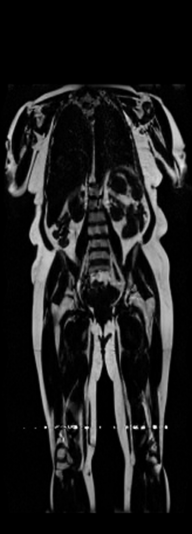

In order to tackle this domain gap, we leverage a registration network [79] paired with a X-Diffusion to achieve DXA to MRI slice generation. [79] introduced a multi-modal image-matching contrastive framework, that is able to learn correspondences between DXA and middle coronal MRI slices. These networks extrapolate the DXA scan by a transform to the coronal MRI slice by harnessing the embedded patterns and features of the DXA and the coronal MRI mid-slice. X-Diffusion is then trained on the registered DXA () and corresponding MRI slices in () in the target MRI volumes and is able to produce precise MRI volumes that align with the DXA scans (see Figure 5 left). The other details are similar to Section 3.2 and Section 3.3.

Notably, X-Diffusion achieves state-of-the-art dB for a few input slices while baselines require more than 60 input slices to achieve similar performance (Figure 7). The margin is more than 12 dB PSNR for the 1-slice input in both the BRATS and the UK Biobank benchmarks (see Table 1 and Figure 6). For reference, two randomly sampled MRIs from UK Biobank would have a PSNR of 15.95 dB 0.36 (on 4800 randomly sampled examples). Omitting the preprocessing step of alignment DXA to MRI, leads to a drop of PSNR on average by 2.87 dB (29.01 dB 26.14 dB). The slices from 3D reconstructed volumes at varying depths and axis of rotation, visually match the ground truths for both brain and whole-body scans (see Figures 4 and 5 left). We also plot the error map (Figure 3) and the spread of the error (Figure 5 right) of such X-Diffusion generations to highlight the differences with the ground truth MRIs.

Preservation of Spine Curvature. For the spine segmentation on UK Biobank, we use a UNet++ model [83] with Dice Loss. We use a model trained to predict curves on DXA on UK Biobank [11]). We measure the Pearson correlation factor [11] of spine curvature measured on the generated MRIs where the input is a single MRI coronal slice, a single sagittal slice, or from the paired DXA, against the curvature of reference real MRIs of the same samples. The correlation coefficients are 0.89 for the coronal MRIs, 0.88 for the sagittal MRIs, and 0.87 for the DXAs on the test set of 308 human-annotated angles. We can then bin the curvature of the spines under different scoliosis categories based on human-annotated angles: mild: , moderate: , and severe . We show the results in Figure 8. This illustrates that the generated MRIs preserve the spine curvature from normal to severe scoliosis cases. Additional details about spine curvature are provided in supplementary material.